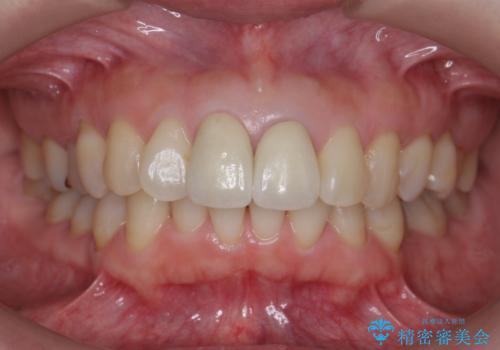

結果、気になっていた色と角度が良くなり、大変喜んでいただけました。

右上1はひっこめた量が大きかったため、反対側の1番と切端をそろえるのに、多少長さは長くなりました。

右上2、左上2の補綴も提案はしましたが、最小限の本数で行っていくことになり、右上2の捻転(歯のねじれ)はそのままとなっております。